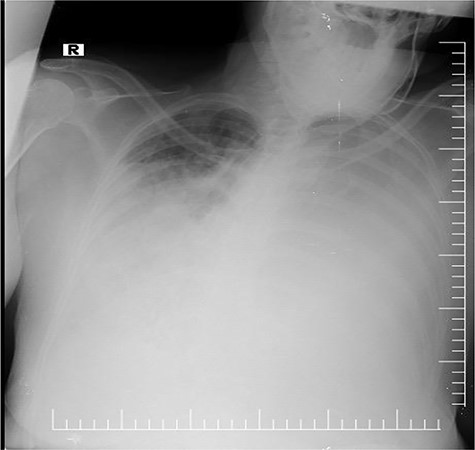

A 60-year-old female patient presented to the emergency with complains of dyspnea, non-productive cough and chest pain for 2 months. There is no history of hemoptysis, weight loss and substance abuse. On physical examination, oxygen saturation was 64%, blood pressure was 170/110 mm Hg, temperature was 97.9°F (36.6°C) and blood sugar was normal. Local examination of the chest revealed limitation in chest movement and decreased tactile focal fremitus on both sides of the chest. On percussion, dullness on both sides of the chest was noticed. On auscultation, decreased breath sounds on both sides of the chest were detected and the apex beat of the heart was displaced on the right side. The blood tests performed in the emergency room were in normal range. She underwent radiological evaluation with chest X-ray that revealed diffuse infiltration on both lungs (Fig. 1). Thoracic echocardiography revealed huge mediastinal mass with dextrocardia. This was followed by chest computed tomography (CT) that showed bilateral diffuse mediastinal mass, which involves fatty tissue containing soft tissue streaks that probably represent islands of normal thymic components with no infiltrations (Figs. 2–3). We concluded that the only curative treatment of thymolipoma is surgical excision. Unfortunately, despite the patient being told about the surgical procedure, she did not give the permission and passed away a week later due to secondary compression to the lungs.

Chest X-ray revealing bilateral opacity in the mediastinum mimicking pulmonary edema.